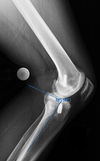

what is this finding called? association?

Segund fx

bony aculsion of anterolateral ligament

pathognominic for acl tear

associated with acl tear 75-100 percent of the time.